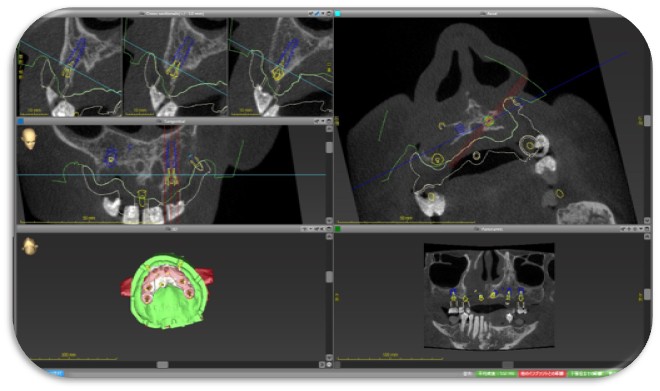

またインプラント治療も安全性に配慮した治療を心掛けており、全症例デジタルシュミレーションソフトによるガイドシステムを用いたインプラント治療が定評で、多くの患者さんの施術をおこなっております。